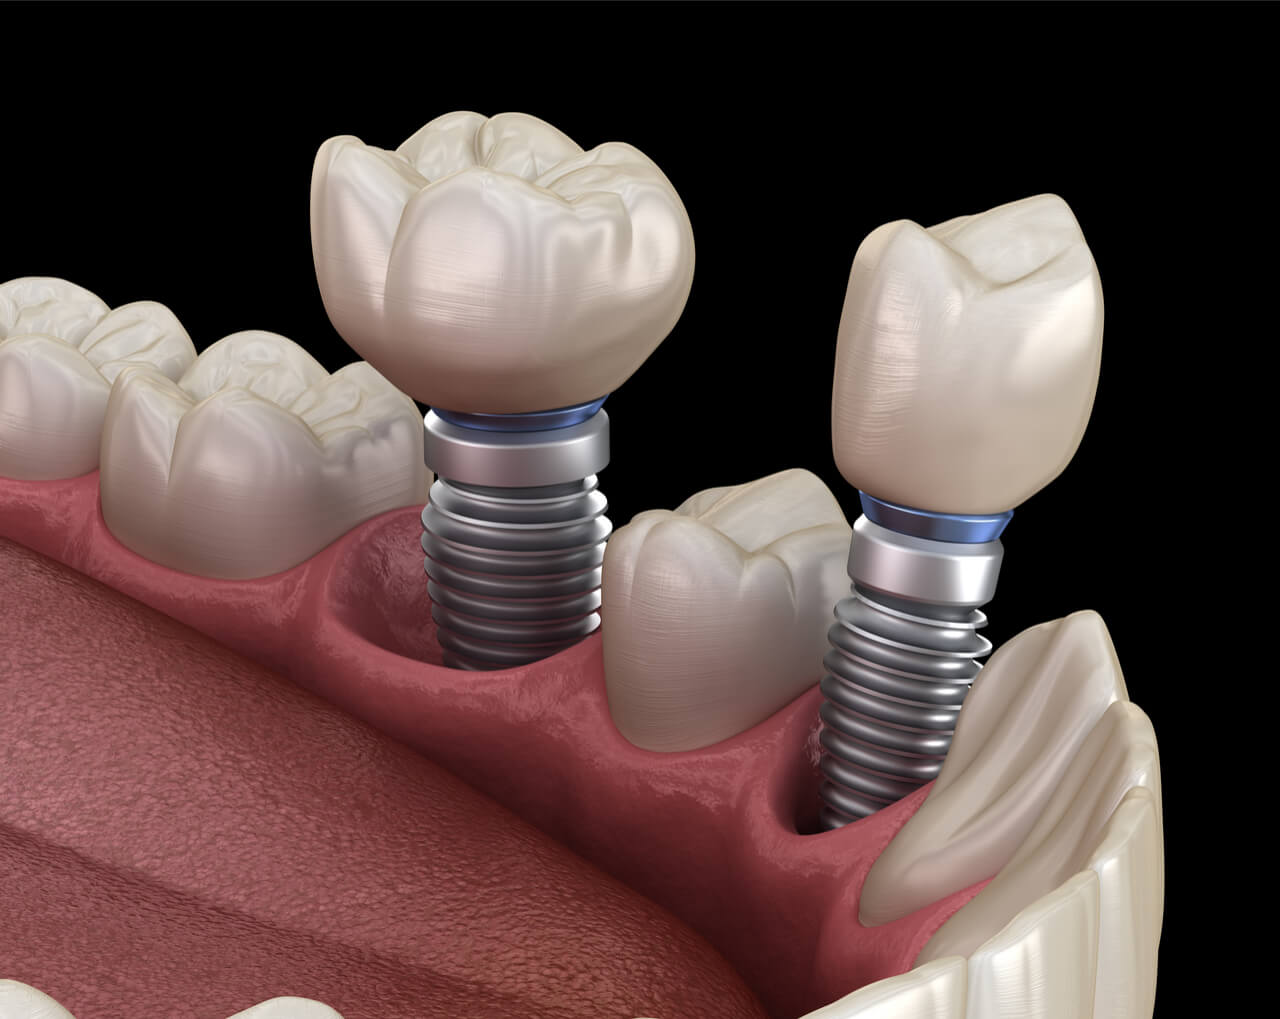

Современная стоматология: Железные зубные импланты